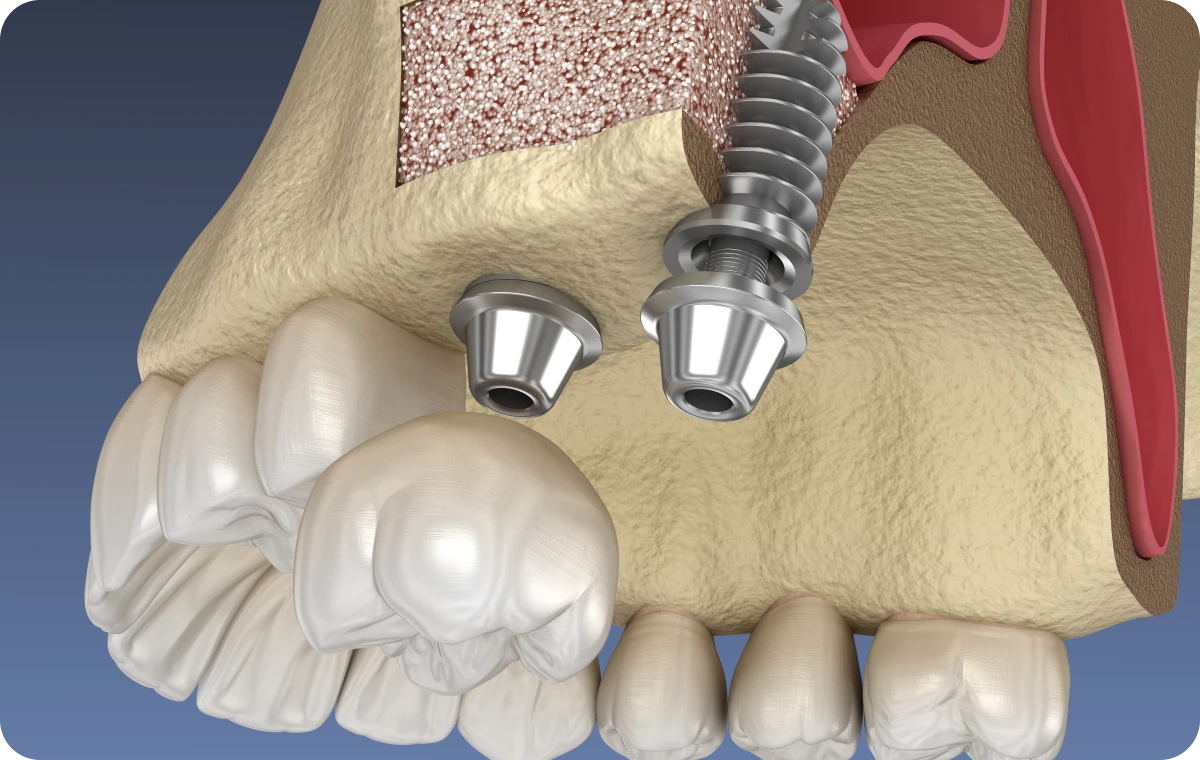

La chirurgie orale regroupe l’ensemble des interventions chirurgicales pratiquées au niveau de la bouche, des dents et des mâchoires. Elle peut inclure des extractions dentaires complexes (comme les dents de sagesse), la gestion de kystes ou de lésions buccales, ainsi que des chirurgies correctrices visant à améliorer la santé et la fonctionnalité de la sphère orale. Ces actes sont réalisés sous anesthésie locale, et dans certains cas sous anesthésie générale, afin d’assurer confort et sécurité aux patients.

Création d’un plan de traitement sur-mesure à l’aide de nos outils : planification esthétique ou implantaire et définition de l’objectif thérapeutique.

- Un bloc opératoire pour anesthésie locale aux normes d’hygiène et d’asepsie en vigueur.